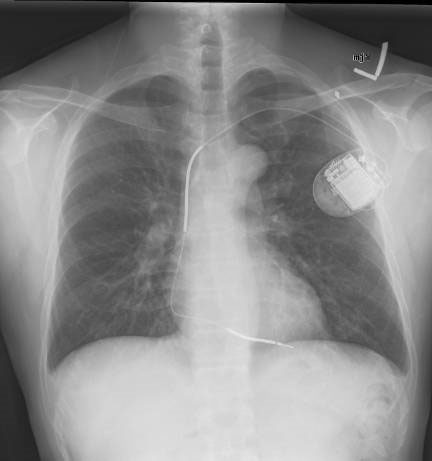

El cardiodesfibrilador implantable profiláctico no disminuyó la mortalidad en insuficiencia cardíaca sistólica de causa no coronaria

Los pacientes estudiados estaban en clase funcional II o III; el 58% tenía colocado un dispositivo de resincronización cardíaca. New England Journal of Medicine, 27 de agosto de 2016